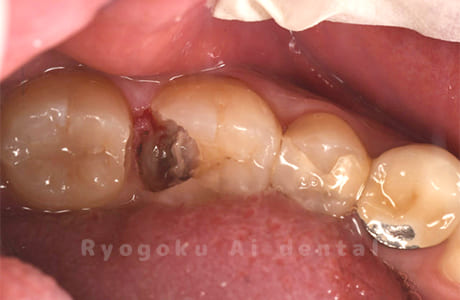

Case06

-

- 原因

- しみる症状がある

- 治療内容

- ジルコニアクラウン

- 治療費用

- 165,000円

他院で治療終了となり、しみる症状があると相談された患者さんです。プラスチックの被せ物の隙間が空いてることとプラスチックの被せ物が大きいため、耐久性と審美性を患者さんと相談し、ジルコニアクラウンで治療を行いました。

<リスク・副作用>

過度の咬合や衝撃で割れることがあります。